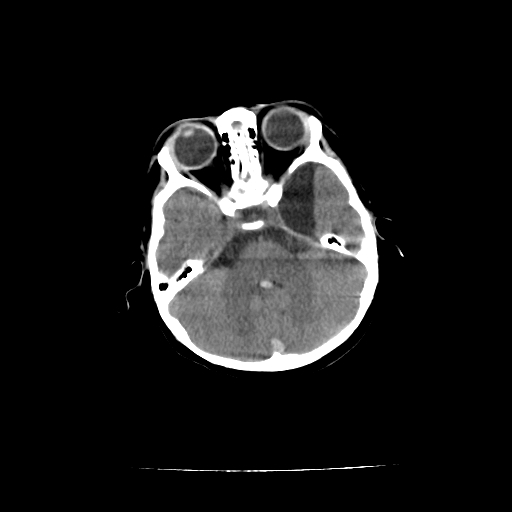

女,10个月,头外伤三天,伤后爱哭闹,吃奶少,睡觉不踏实。

左侧颞极蛛网膜囊肿

1)左侧颞极蛛网膜囊肿。2)第四脑室出血?

1、左侧颞极蛛网膜囊肿;2、第四脑室出血?3、右侧顶叶脑裂畸形伴灰质异位?

1)左侧颞极蛛网膜囊肿。2)第四脑室内高密度影,性质待定。